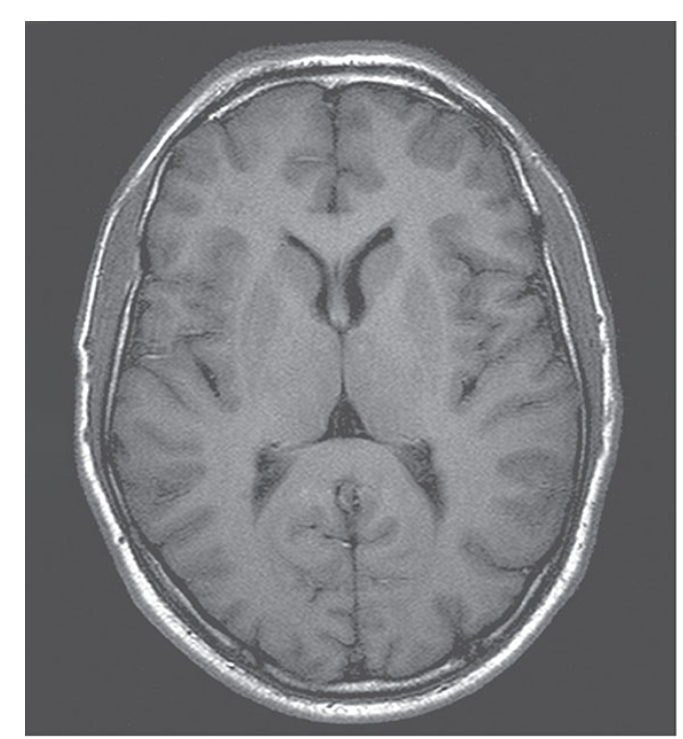

Axial T1-weighted inversion recovery sequence of the brain